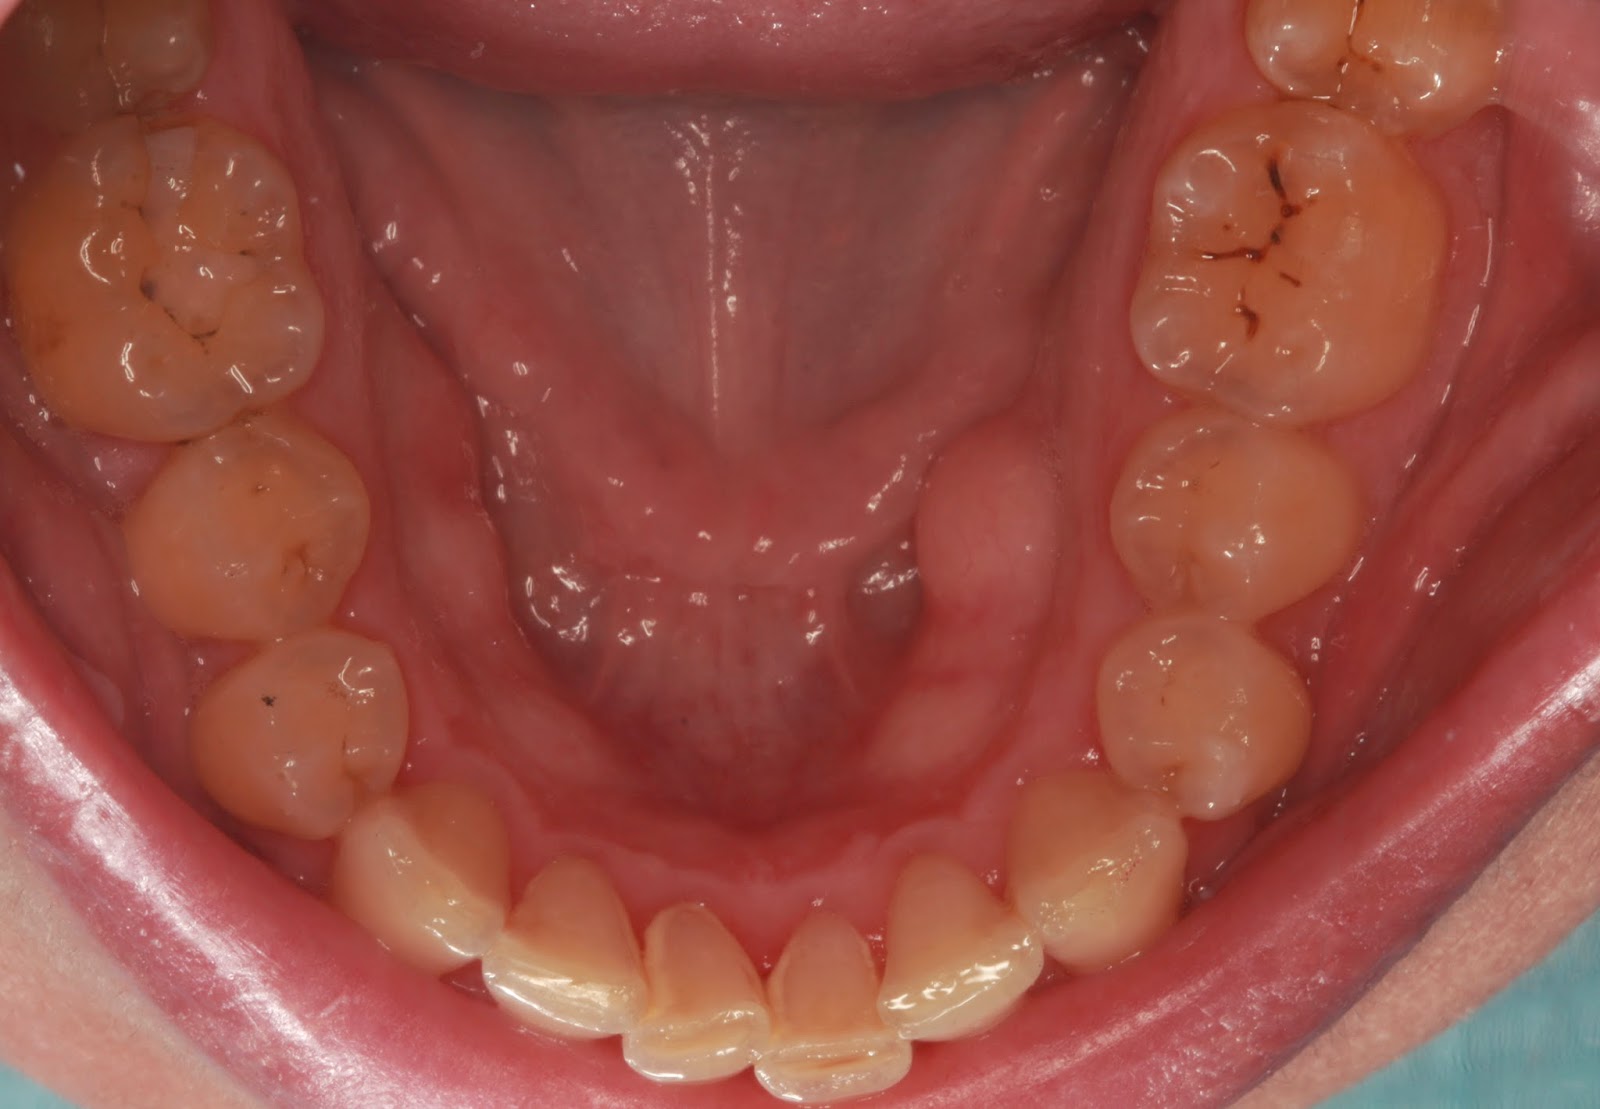

Άνω γνάθος(Torus

palatinus-τορους παλατίνους)

Κάτω γνάθος (Torus

mandibularis-τόρους μαντιμπιουλάρις)

Βλέπουμε λοιπόν ότι τα Τοri είναι εξοστώσεις,δηλαδή οστέινες προεξοχές,δηλαδή κόκαλο, που εντοπίζονται στο κέντρο ή στα πλάγια της άνω γνάθου και στα πλάγια συνήθως της κάτω γνάθου.